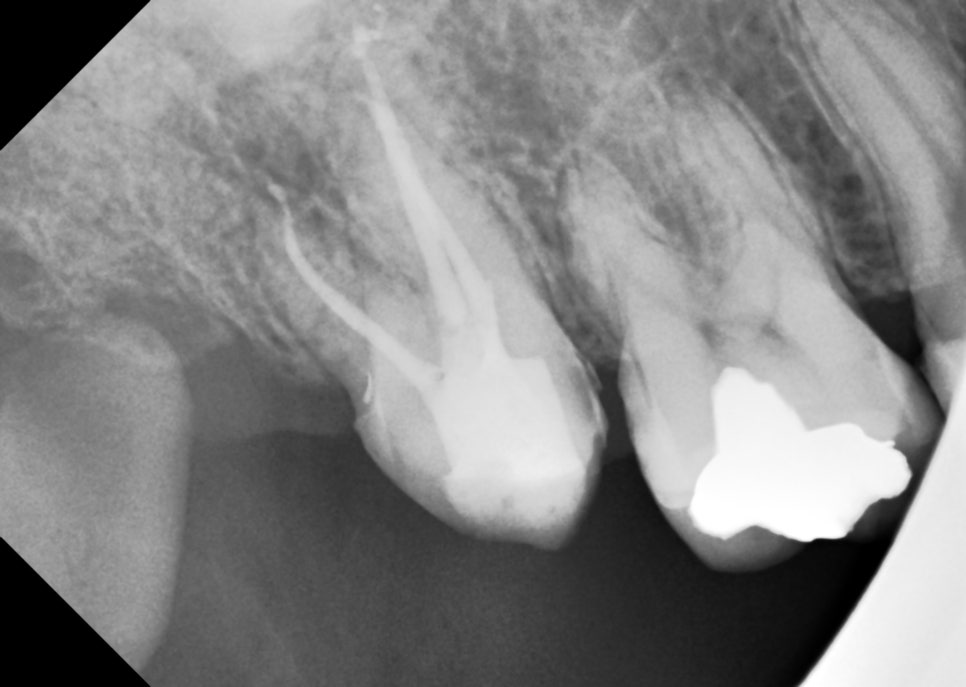

받아보니 17번 ㅋㅋㅋㅋㅋ 진짜...

이전 치과에서 해놓은 AO가 좀 아쉽죠

치아 앞쪽을 너무 많이 파먹었습니다.

근관도 안찾아놓으셨구

미세한 신경관인 MB2는 없었습니다

다행히.

마무리도 잘 됐습니다.

코어 레진은 또 해서 보내드렸습니다